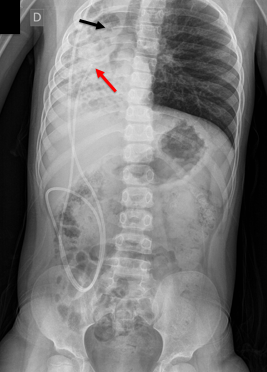

Paciente de 3 años, con antecedente de tumor de fosa posterior (TFP) e hidrocefalia, que debutó con síntomas de hipertensión endocraneana y ataxia de 3 semanas de evolución. Consultó a otra Institución, donde se colocó una DVP y se derivó a nuestro Hospital. Se realizó de forma programada resección del TFP sin complicaciones y con buena evolución. A los 5 meses de la colocación de la válvula, consultó por cefalea, náuseas y vómitos. Se estudió con Tomografía cerebral, que evidenció dilatación ventricular, y radiografías del sistema (Figura 4) que mostraron la ubicación intracardiaca del catéter distal. Se completaron los estudios con una tomografía de tórax (Figura 5) que informó la posición anómala del catéter distal, que se introducía en las cavidades cardiacas derechas, posteriormente en la arteria pulmonar, volviendo a las cavidades derechas e introduciéndose en la vena cava inferior con localización de la punta del catéter a nivel de la vena suprahepática derecha. No se observaron trombos relacionados con el catéter. Junto a los Servicios de Intervencionismo y Cirugía Cardiovascular se realizó la revisión valvular bajo monitoreo cardiológico continuo y radioscopia. A través de una incisión paralela a la válvula se retiró el catéter distal y se lo recolocó a la cavidad peritoneal. El paciente evolucionó favorablemente y fue dado de alta.

Figura 4: Radiografía de Tórax y abdominal del Caso 2, que evidencian la migración intra cardiaca del catéter distal de la derivación ventrículoperitoneal.